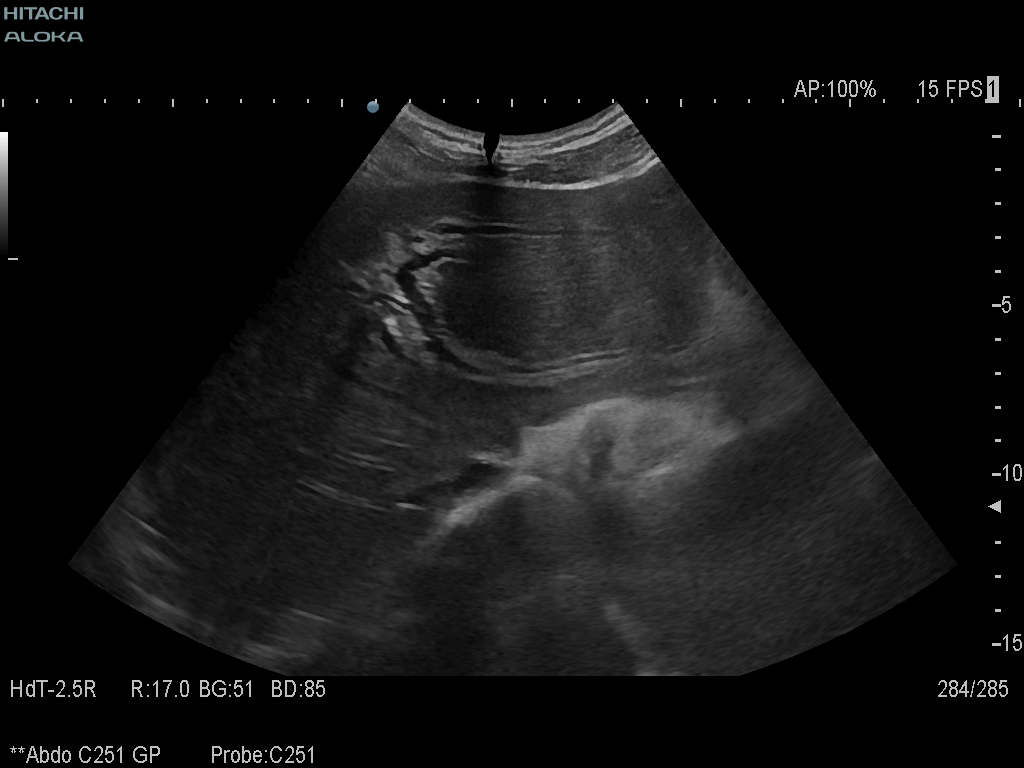

Student Image Challenge 69October 16, 2020ECMUS Bylaw (2)October 27, 2020 Student Image Challenge 70 Fig.01 Fig.01 Fig. 02 Student Image Challenge #70 1 / 1 Student Image Challenge #70 What can cause this ultrasound aspect ? Simple hepatic cyst Acute hepatitis Extrahepatic cholestasis Intrahepatic cholestasis It is a normal aspect of the liver Incorrect ....Please see the correct answer highlighted Correct: Extrahepatic cholestasis Your score isThe average score is 0% LinkedIn Facebook VKontakte 0% Restart quiz Case courtesy of Prof Adrian Saftoiu EFSUMBAdmin Related postsStudent Image Challenge 112Read more Comments are closed.